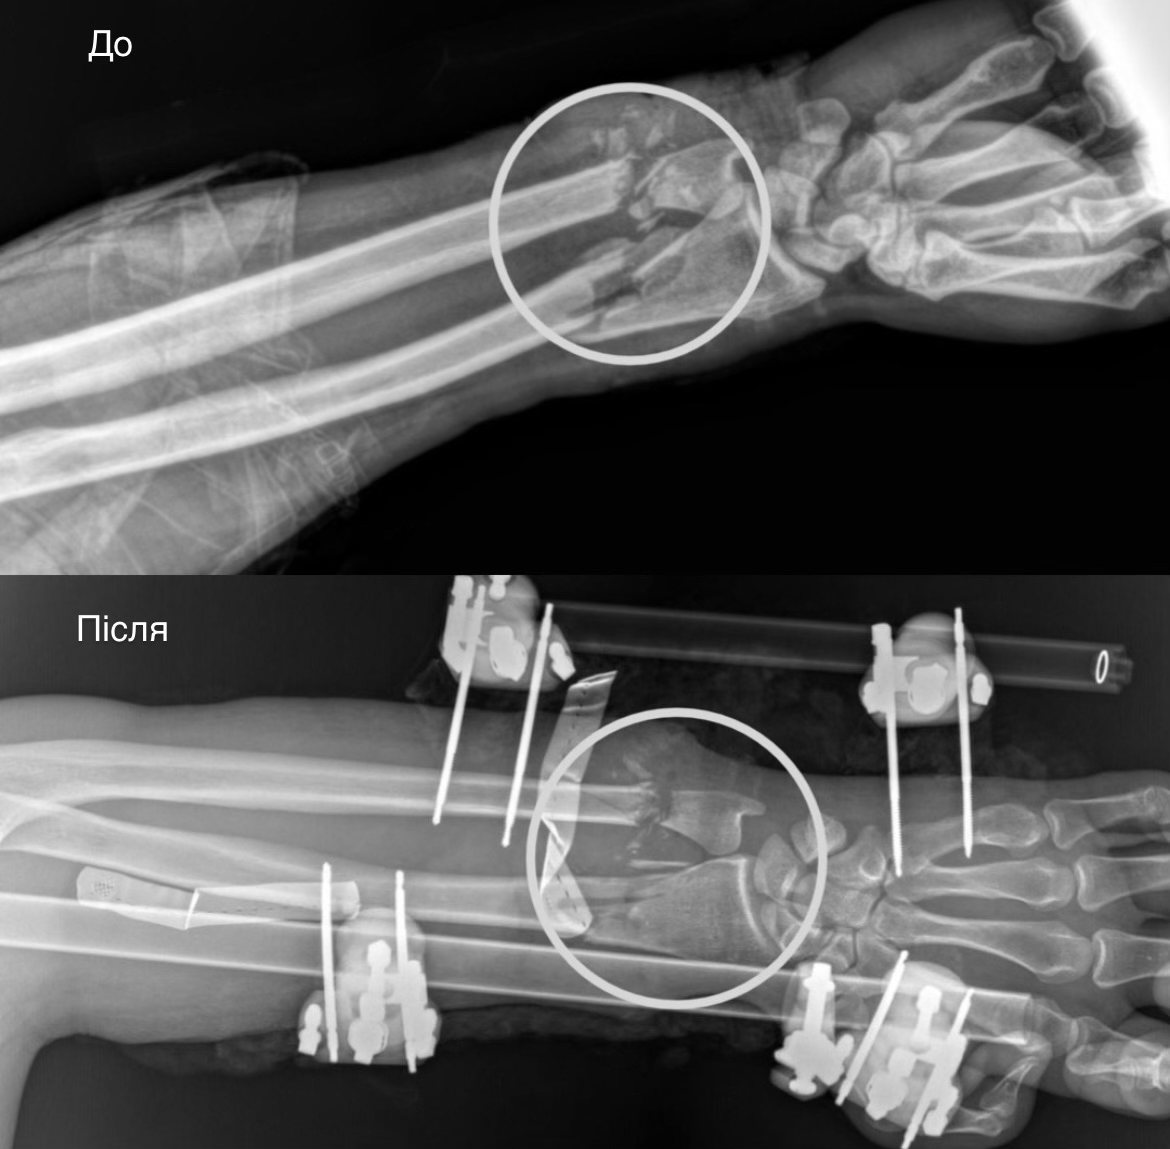

Стан був украй важкий: рука трималася фактично лише на шкірі. Артерії були повністю перерізані, кістки зламані, пошкоджені м’язи, сухожилля та нерви. За порятунок кінцівки взялася команда лікарів різних спеціальностей.

Спочатку травматологи зафіксували переломи спеціальним апаратом. Потім судинні хірурги відновили кровообіг, зшили пошкоджені судини.

На наступному етапі лікарі відновили м’язи та сухожилля, щоб повернути рухи згинання й розгинання. Пошкоджені нерви підготували до ще однієї операції, яку планують провести через один-два місяці. Завершили операцію пересадкою власної шкіри пацієнта, щоб закрити рану.